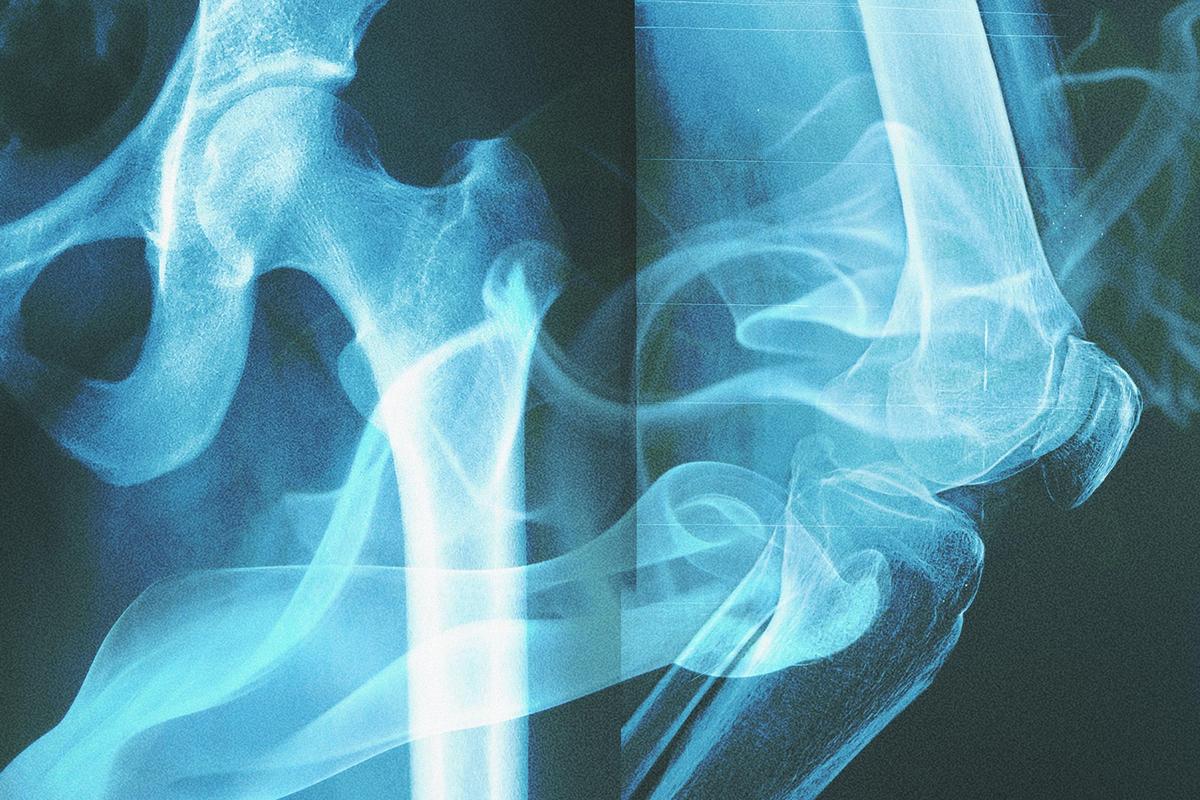

Imagine this: Hundreds of years ago, a man lit a cigarette, and the smoke drifted away with the wind. Centuries later, scientists can still find that “smoking memory” preserved in his bones.

A research team from the University of Leicester in the UK published their findings in the journal Science Advances, reporting that smokers leave unique molecular signatures in their bones that, even after centuries of burial, can still reveal their smoking habits.